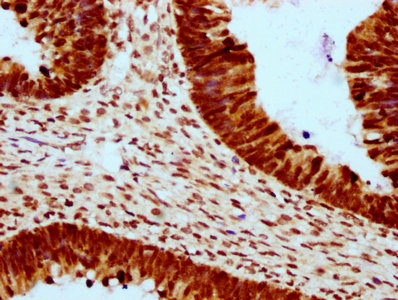

IHC (Immunohistochemistry)

(IHC image of AAA234935 diluted at 1:10 and staining in paraffin-embedded human ovarian cancer performed on a Leica BondTM system. After dewaxing and hydration, antigen retrieval was mediated by high pressure in a citrate buffer (pH 6.0). Section was blocked with 10% normal goat serum 30min at RT. Then primary antibody (1% BSA) was incubated at 4 degree C overnight. The primary is detected by a biotinylated secondary antibody and visualized using an HRP conjugated SP system.)